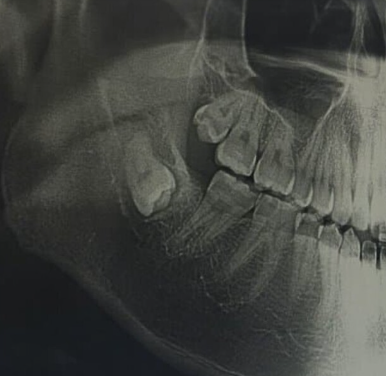

어느 날 갑자기 잇몸 구석이 욱신거리기 시작했다면, 그것은 인류 진화의 흔적이자 치과 의사들의 영원한 숙제인 사랑니가 존재감을 드러낸 신호일 가능성이 큽니다. 사랑니는 예쁘게 나서 제 역할을 하면 좋으련만, 보통은 좁은 잇몸 틈바구니에서 옆 치아를 괴롭히거나 매복되어 염증을 일으키기 일쑤입니다.

하지만 잇몸을 째고 치아를 쪼개서 꺼내야 하는 매복 발치나 복잡 발치로 넘어가면 비용은 3만 원에서 5만 원 선으로 올라갑니다. 만약 대학병원 같은 상급종합병원으로 원정을 떠난다면 기본 진찰료가 비싸지기 때문에 비용이 조금 더 추가될 수 있습니다.